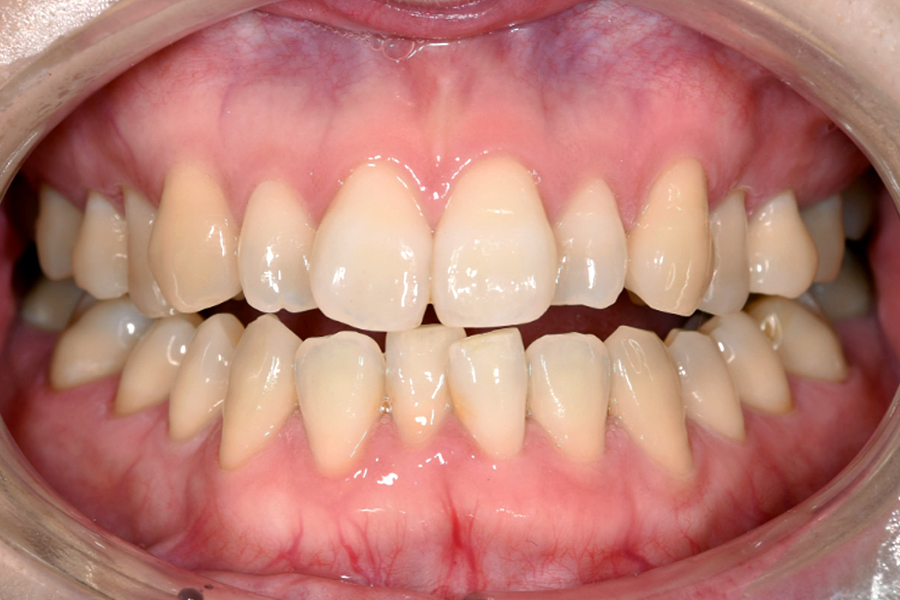

| 主訴 | 見た目を治したい、歯を白くしたい |

|---|---|

| 治療期間 | 1年6か月 |

| 治療費 | マウスピース矯正と ホームホワイトニングセット 1,022,350円(税込) |

| 治療内容 | 目立ちにくいマウスピース矯正 (非抜歯矯正) 歯と歯の間に隙間をつくることにより、歯列弓を広げながら治療を行いました。 また矯正用マウスピースをトレー代わりにし、ジェルを入れてホームホワイトニングを同時に行っております。 |

| 治療のリスク | ・後戻りする可能性があるのでリテーナーを最低でも矯正期間以上はつける必要があります。 ・ホワイトニング後、一時的に痛みが出る場合があります。 |